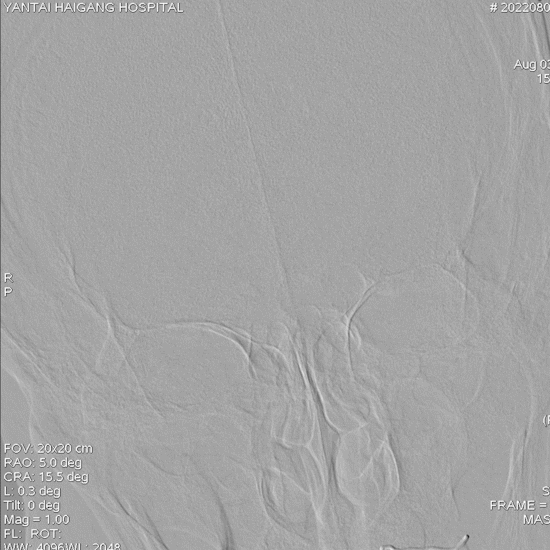

术前造影:

左椎动脉+左颈动脉造影:

右椎动脉造影:

右颈动脉造影:

右椎动脉动脉正侧位: